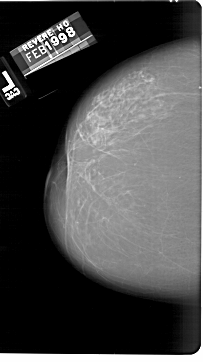

A_1539_1.RIGHT_MLO

RIGHT_MLO LINES 6556 PIXELS_PER_LINE 5041 BITS_PER_PIXEL 12 RESOLUTION 43.5 OVERLAY